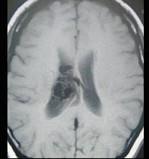

女性,40岁,头晕、头痛两年余,MR检查如图所示,请选择的最可能诊断 ( )A、毛细血管扩张症B、动脉瘤C、动静脉畸形D、毛细血管...

问题 女性,40岁,头晕、头痛两年余,MR检查如图所示,请选择的最可能诊断 ( )

选项 A、毛细血管扩张症 B、动脉瘤 C、动静脉畸形 D、毛细血管瘤 E、海绵状血管瘤

答案 C